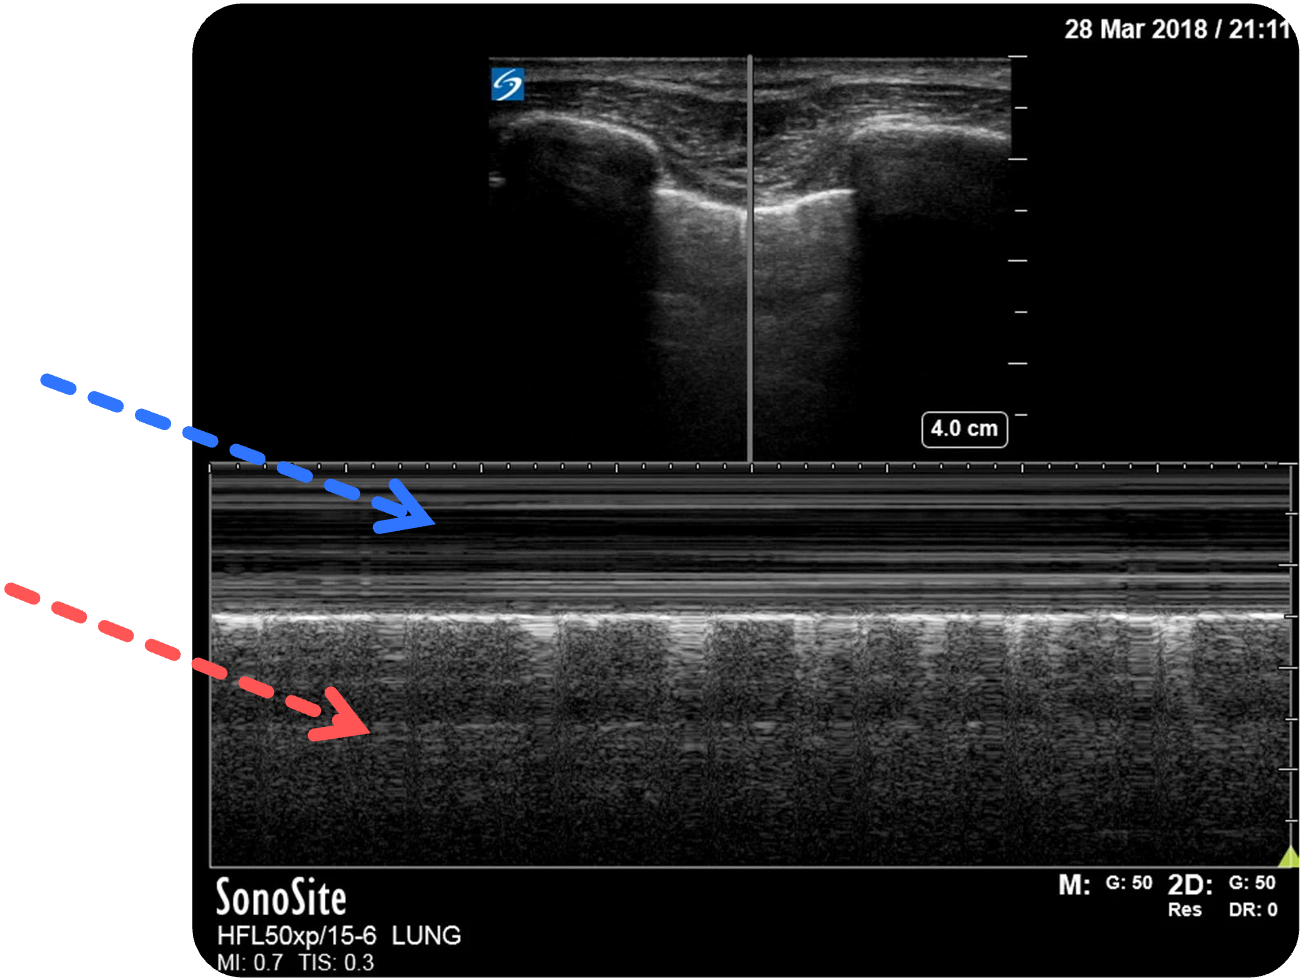

- Seashore-Sign (M-Mode

): ruhige Linien oben (unbewegliche Thoraxwand) (blauer Pfeil) und körnige Struktur (bewegende Lunge ) unten (roter Pfeil)

Figure 3 aus Ketelaars, R., Reijnders, G., van Geffen, GJ. et al. ABCDE of prehospital ultrasonography: a narrative review. Crit Ultrasound J 10, 17 (2018). https://doi.org/10.1186/s13089-018-0099-y. Teilausschnitt des Originalbilds. Der rote und blaue Pfeil wurden hinzugefügt.

Normalbefund im M-Mode :

Wenn eine Darstellung des Pleuragleitens erschwert oder unsicher ist, ist der M-Mode

Im oberen Bereich des M-Mode

Figure 5 aus Ketelaars, R., Reijnders, G., van Geffen, GJ. et al. ABCDE of prehospital ultrasonography: a narrative review. Crit Ultrasound J 10, 17 (2018). https://doi.org/10.1186/s13089-018-0099-y. Teilausschnitt des Originalbilds. Es wurden die Markierungen und Beschriftungen ergänzt.